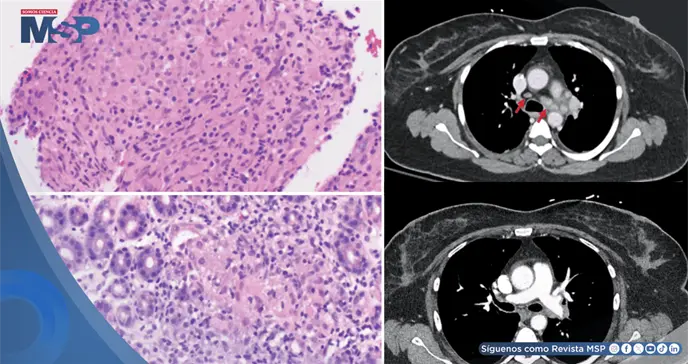

Para determinar la naturaleza de estas nuevas adenopatías, se llevó a cabo una evaluación diagnóstica exhaustiva y multidisciplinaria. Se realizó una endoscopia digestiva alta, cuyas biopsias mostraron la presencia de granulomas no caseificantes en el estómago.

De forma paralela, se practicó una broncoscopia con biopsia de los ganglios anormales mediante ecografía endobronquial (EBUS-TBNA). El análisis histopatológico de estas muestras confirmó un hallazgo similar: tejido linfático benigno con granulomas no caseificantes, sin ninguna evidencia de células cancerosas.

Todos los estudios microbiológicos especiales para descartar infecciones como tuberculosis u hongos resultaron negativos, al igual que los análisis sanguíneos para enfermedades autoinmunes o sarcoidosis clásica.